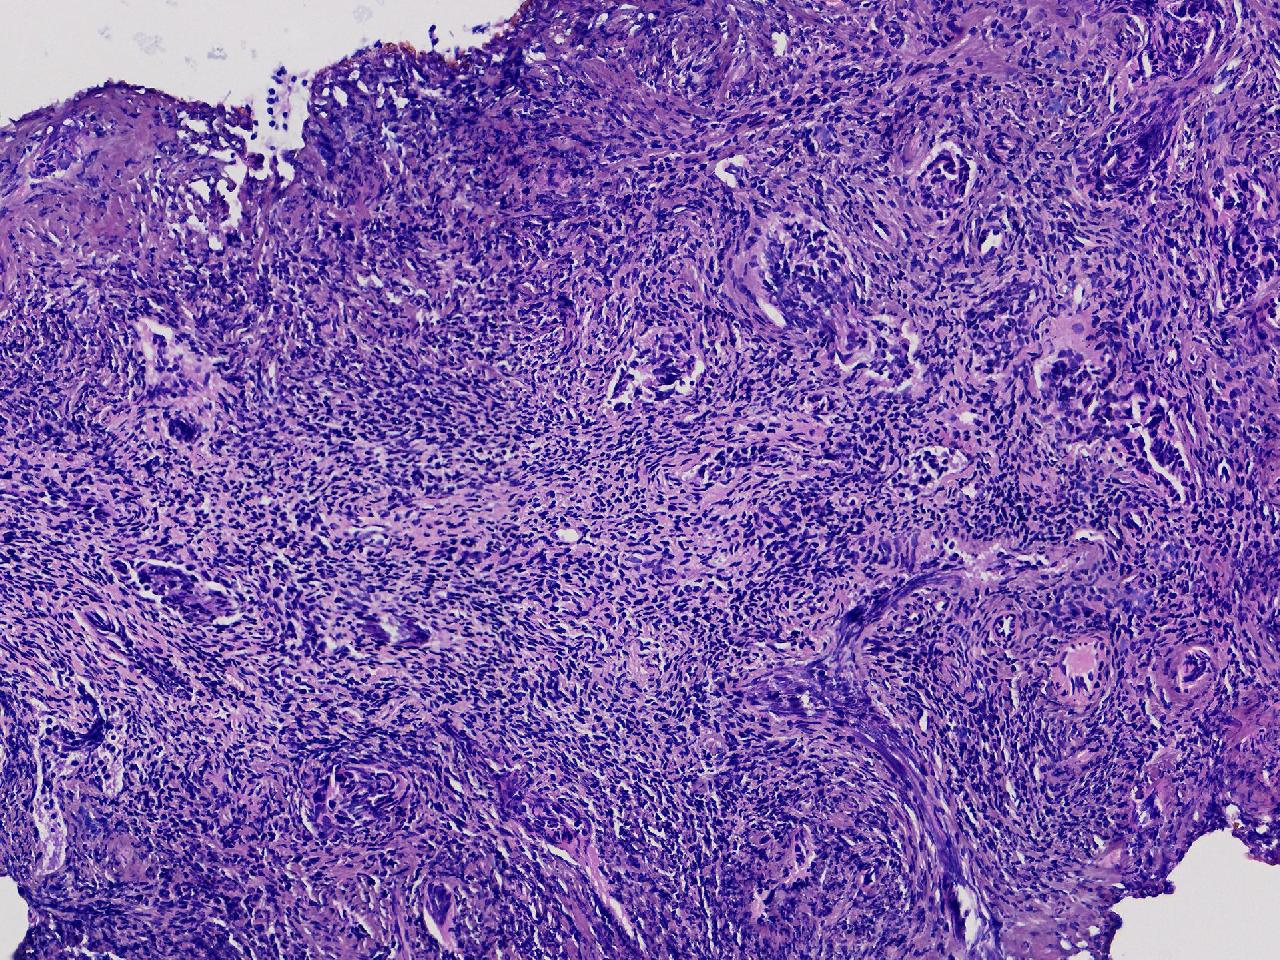

性别

女

年龄

56岁

彩超示宫腔内见5x3ml的团状偏强回声结节,边界清。

宫腔息肉?

灰粉色不整形软组织多块,0.5X0.3X0.3厘米。

首先考虑子宫内膜息肉,有些区域间质细胞较密,找找看有没有核分裂。

彩超提示强声团体积不小,待完整切除送检再综合诊断。